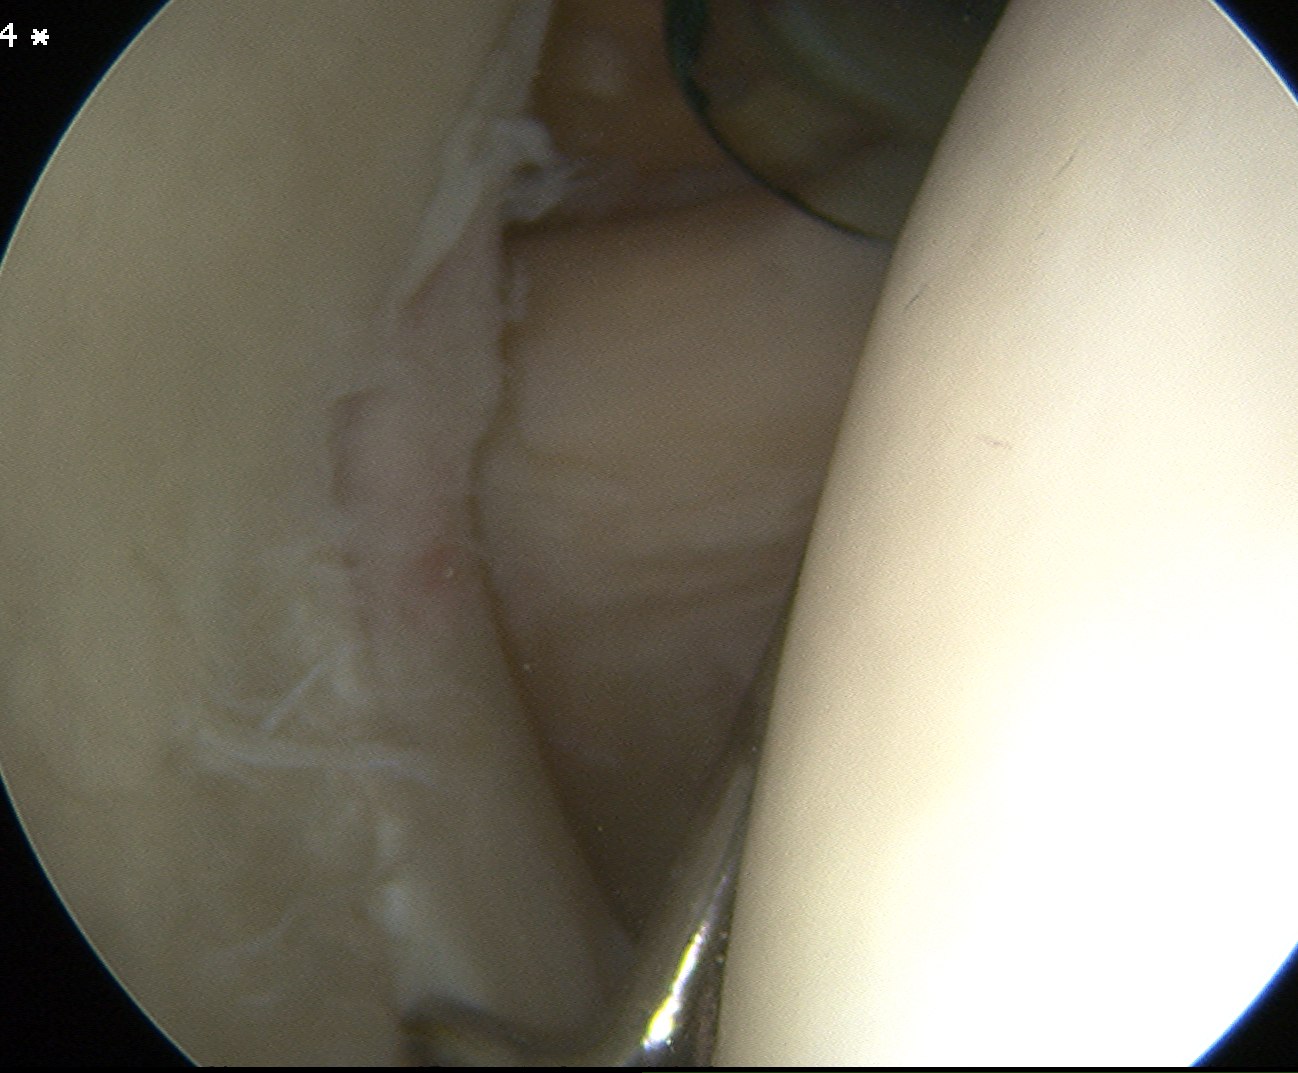

Subacromial space

Portals

| Posterior | Lateral subacromial portal |

|---|---|

|

Redirect posterior portal Under acromion |

Midportal clavicle |

| Usually viewing portal |

Rotator cuff repair / Subacromial decompression Distal clavicle resection |

![]() |